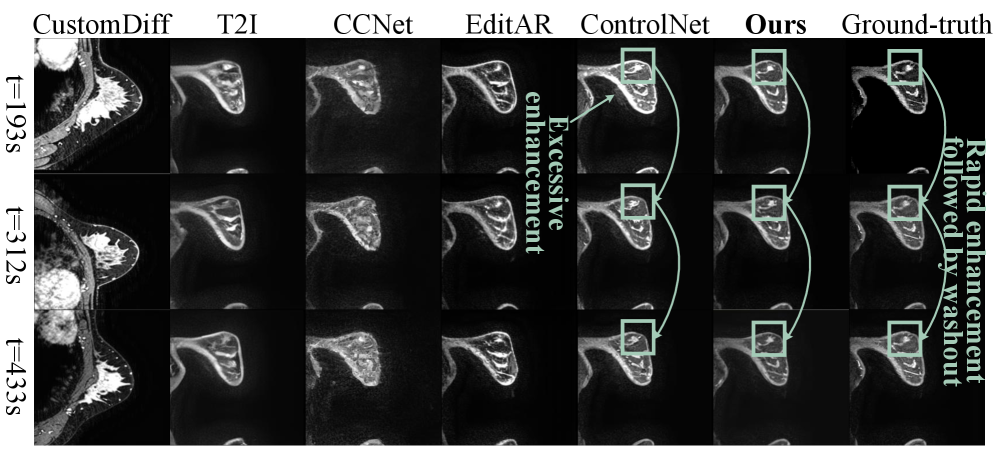

Visualization Results Analysis As shown in Fig.4 and Fig.5, the visualization sequences of both datasets demonstrate that our method achieves high spatial reality and natural kinetics, both closely matching the ground-truth. CustomDiff and T2I generated images with severe deviations from the ground-truth, suffering from blurred organ contours and distorted dynamic enhancement gradients of contrast agents. CCNet failed to converge, leading to excessively smooth images, severe spatial structural distortion, and the appearance of color blocks, which is consistent with the previously analyzed characteristic of high PSNR. EditAR and ControlNet have normal spatial structures, but their kinetics both deviate from the normal pattern. More visualization results are in Supplementary.

Figure 5: Visualization results in Breast DCE-MRI: The visualization results achieves temporal consistent (connected green boxes) with contrast agent kinetics, demonstrating superior fidelity in breast DCE-MRI sequence generation.

7.2.3 Visualization Results for Different Enhancement Patterns in Breast DCE-MRI

The two breast DCE-MRI visualization cases shown in Fig.13 and Fig.14 demonstrate that our CEKWorld simulates clinically meaningful kinetic patterns, showing strong potential for downstream risk-stratification tasks since lesion malignancy is closely associated with characteristic enhancement patterns [36, 44]. In both figures, our model accurately reproduces the temporal trajectories observed in ground-truth DCE-MRI sequences, whereas competing methods exhibit severe issues such as incorrect enhancement magnitude, temporal shifts, or lack of temporal evolution. In Fig.13, the ground-truth exhibits a gradually rising and persistently elevated curve, typical of a persistent enhancement pattern, often associated with benign or low-risk lesions. Our method produces consistent, sustained enhancement across all time points, faithfully matching the true kinetics. In contrast, EditAR shows enhancement delay, and ControlNet lacks any meaningful temporal progression, failing to reproduce the low-risk kinetic profile. This demonstrates our model’s ability to reconstruct benign-like temporal behavior. In Fig.14, the lesion shows rapid initial enhancement followed by clear washout, a hallmark of malignant or high-risk lesions. Our method correctly captures this dynamic pattern: a sharp early rise followed by a decline consistent with the ground truth. EditAR suffers from excessive enhancement and fails to show the washout phase, while ControlNet exhibits collapsed or weakened dynamics, failing to reproduce the malignant-typical kinetic transition. Together, these two visualization examples show that our method not only preserves spatial fidelity but also faithfully models critical DCE-MRI temporal dynamics. Because low- and high-risk lesions exhibit fundamentally different enhancement trajectories, the ability of our model to reconstruct these dynamics suggests strong potential for downstream tasks such as risk stratification, benign-vs-malignant discrimination, and clinical subtype prediction.